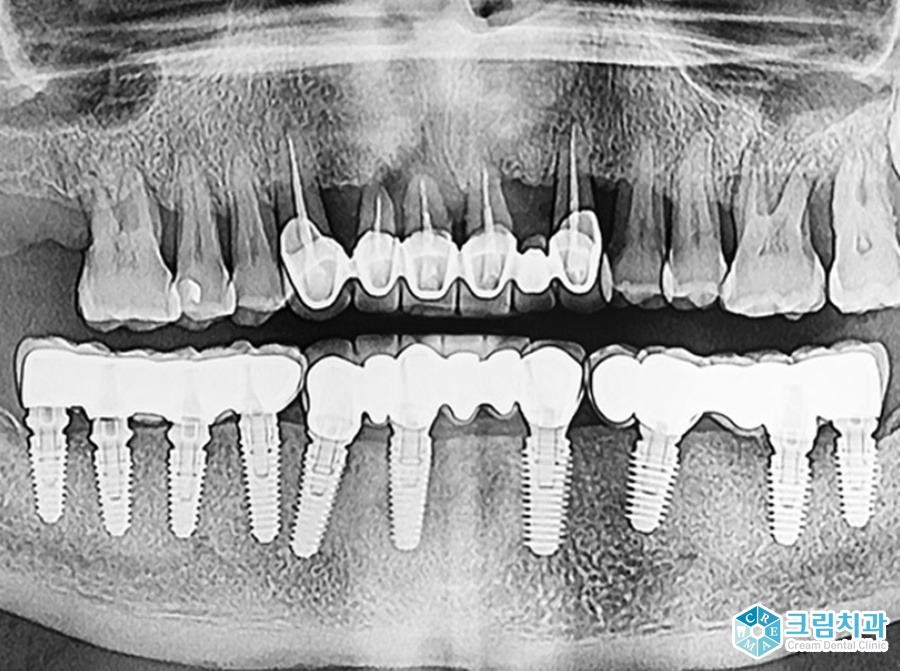

전체임플란트는 상실된 치아 전체에 임플란트 수복물을 씌우는 것을 말합니다. 많은 분들이 상실된 치아 수만큼 임플란트를 식립하는 것으로 생각하시는데요.

아래위 각각 8~10개의 픽스처(인공치근)를 식립하고 치아 모양의 수복물을 씌우게 됩니다.

인공치근이 잇몸 뼈와 단단하게 유착되기 때문에 자연치아와 유사한 유지력을 갖고, 씹는 힘 또한 자연치아의 80%에 달합니다.

임플란트 틀니가 치아의 50%, 일반 틀니가 치아의 10~20% 저작력을 갖는 것에 비해 상대적으로 상당히 높은 수치지요.

이물감 또한 거의 없어 기존 틀니 사용에 불편함을 느끼시는 분들이 전체임플란트를 고려하시는 경우가 많습니다.